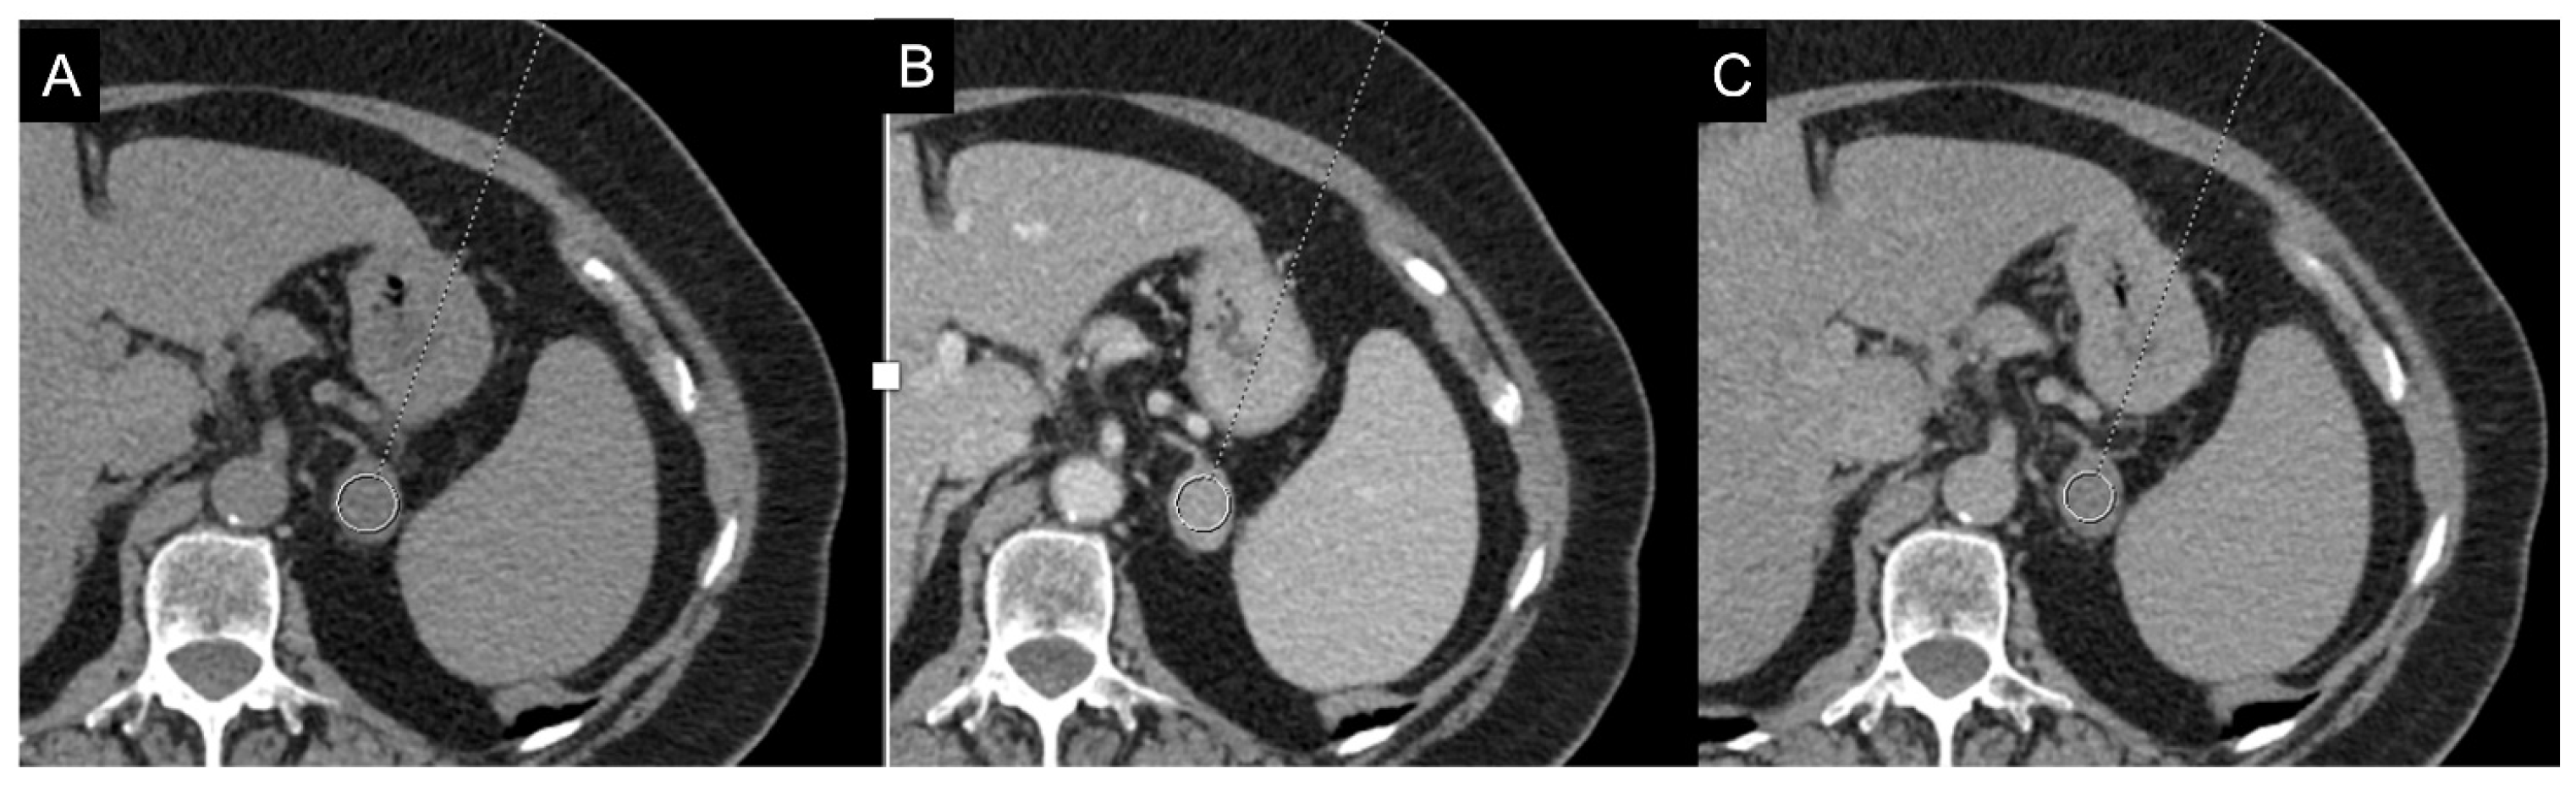

Figure 4.

36-year-old man with history of night sweats, hypertension, and tachycardia due to pheochromocytoma (arrow). Non-contrast CT shows an inhomogeneous right adrenal mass > 20 HU (A). In the arterial phase (B), the mass shows intense enhancement of the solid components with persistent enhancement. In the late phase (C), absolute contrast medium washout is <50%.